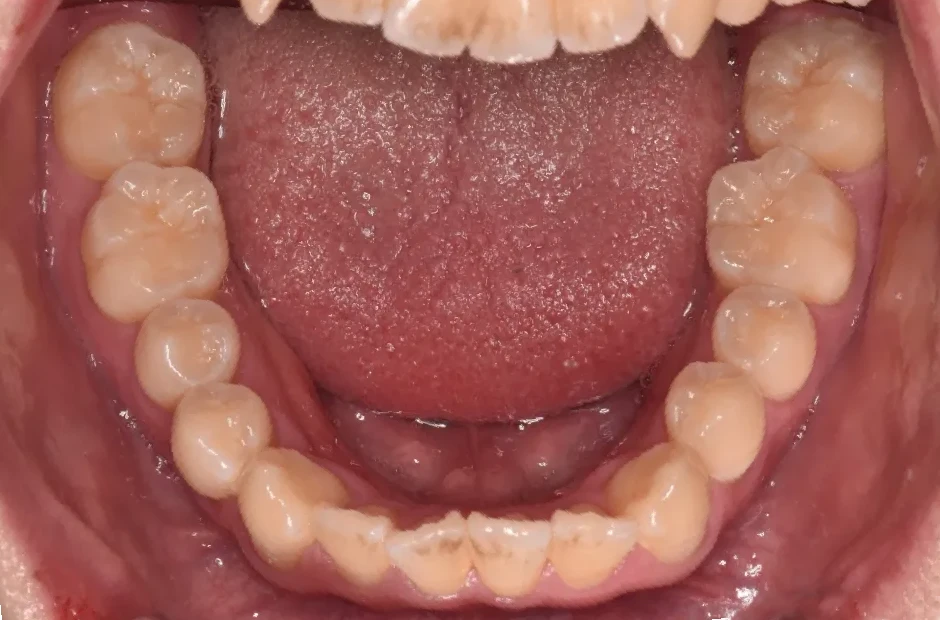

治療症例

ブラケット矯正

前歯部反対咬合

| 診断名・主訴 | 前歯部反対咬合 |

|---|---|

| 年齢・性別 | 14歳・男性 |

| 治療期間・回数 | 1年2か月 |

| 治療に用いた主な装置 | ブラケット矯正 |

| 抜歯部位 | なし |

| 治療費 | 60万円(税抜) |

| リスク・副作用 | 装置による違和感・疼痛・歯肉退縮・歯根吸収・虫歯のリスクなど |

治療前

治療後